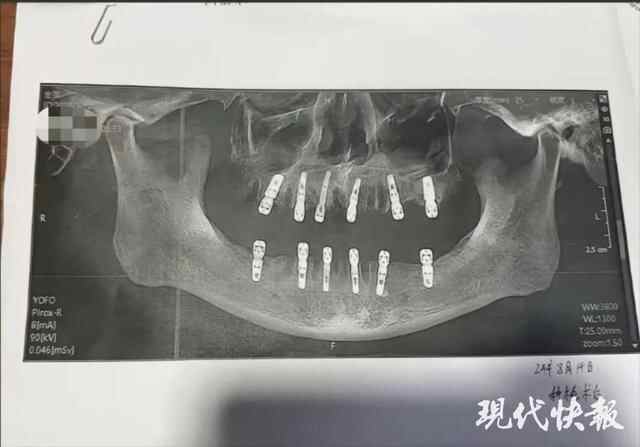

据舒女士发布的信息显示,其父亲黄某8月14日在德维口腔医院接受牙科手术。根据种植手术同意书显示,本次治疗拔牙23颗、种植牙齿12颗,并且均为即刻修复,即“当天拔、当天种”,负责进行治疗的医师为袁某。

然而,据黄某的种植手术同意书,在其接受的手术中,有多颗臼齿在拔除当天就进行了种植,与工作人员介绍的注意事项不符。